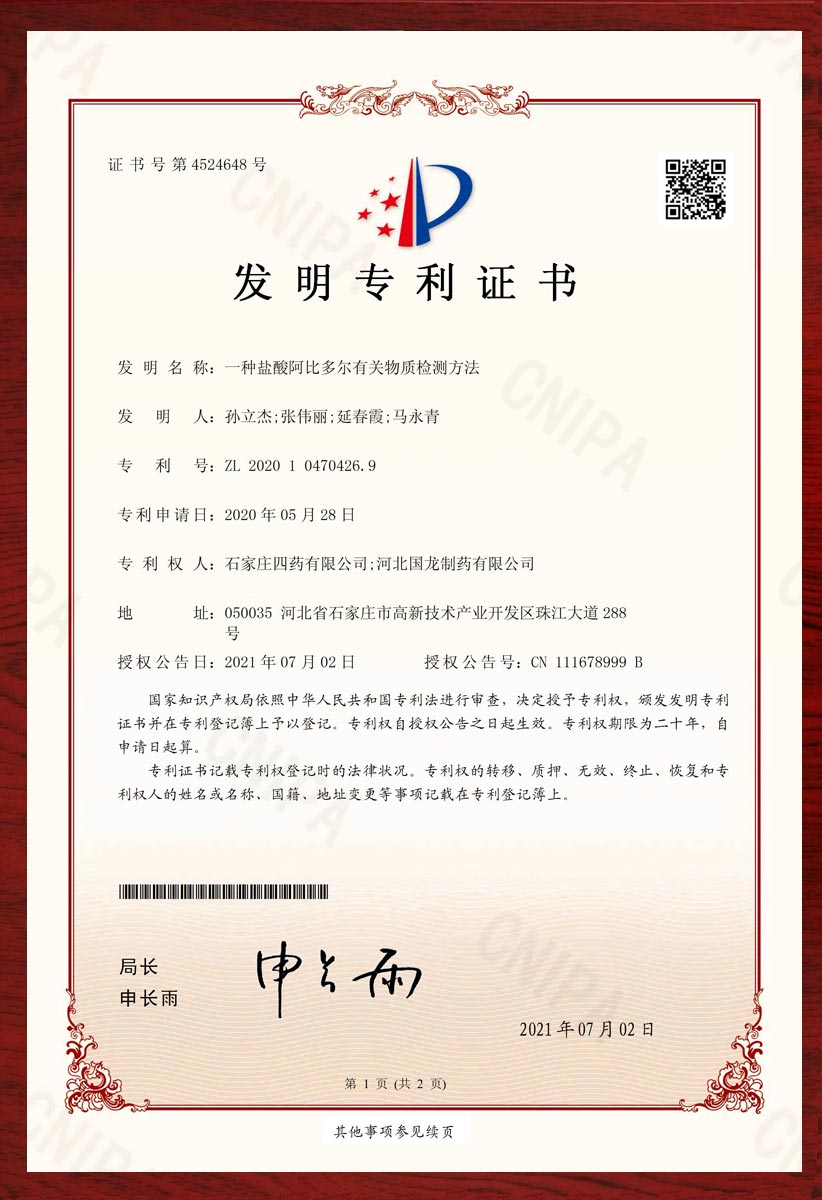

专利证书